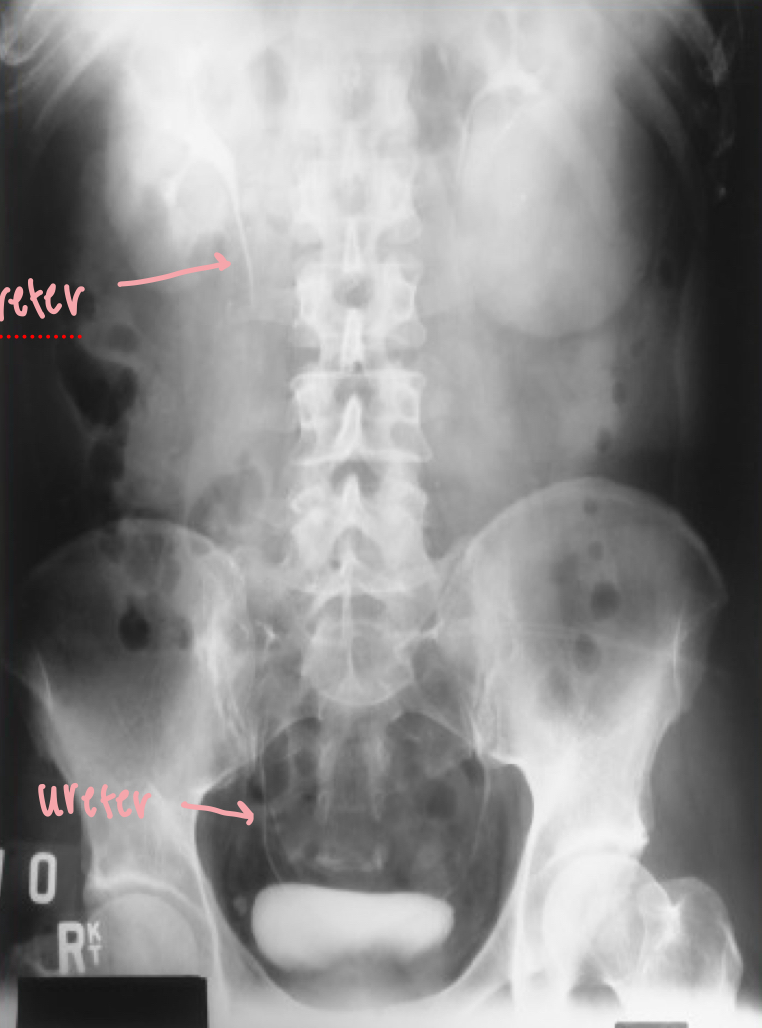

What position is this?

IVU AP

What is this X-ray demonstrating?

IVU AP